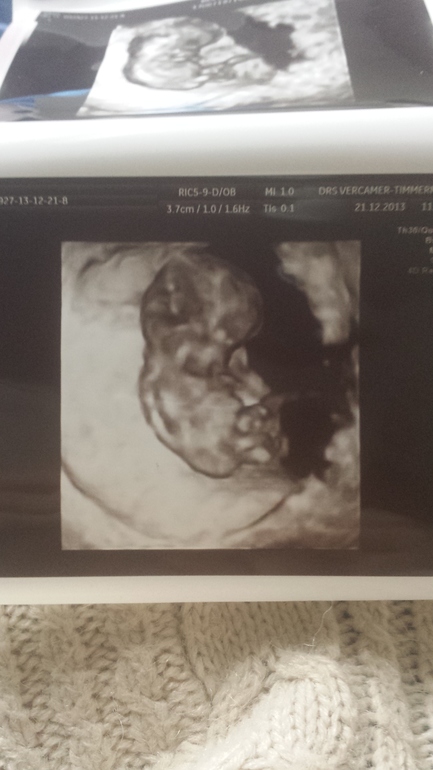

Ой,а я и не представляла...Значит и мой уже такой!!! Прелесть!!!Это 3 д?

Такой щекастенький)))) весь в папу)))) смотрела фотки родственницы одной на этом же сроке у них не такие щечки)))))